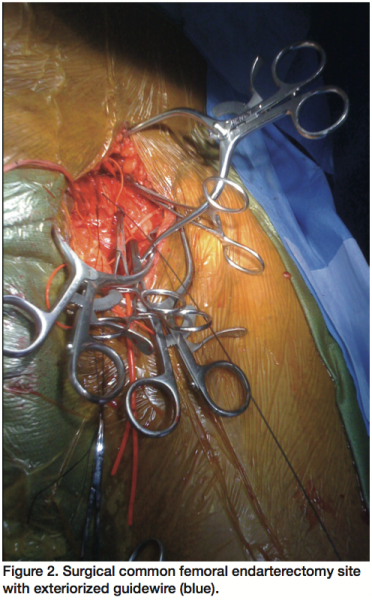

Aortography with runoffs revealed a long segment of total occlusion from the proximal left common iliac artery (CIA) to the distal common femoral artery (CFA) (Figure 1). However, there was reconstitution of the left profunda femoris artery via extensive collaterals, which further supplied collaterals to a patent popliteal artery and one vessel runoff into the left foot. The patient was discharged the following day with medical therapy including dual antiplatelet therapy, statin, nicotine replacement, exercise rehabilitation, and outpatient follow up scheduled in vascular medicine and surgery clinics. After 6 months of failed conservative therapy, patient returned for a hybrid endovascular and surgical procedure due to high risk of isolated surgical approach related to medical comorbidities.